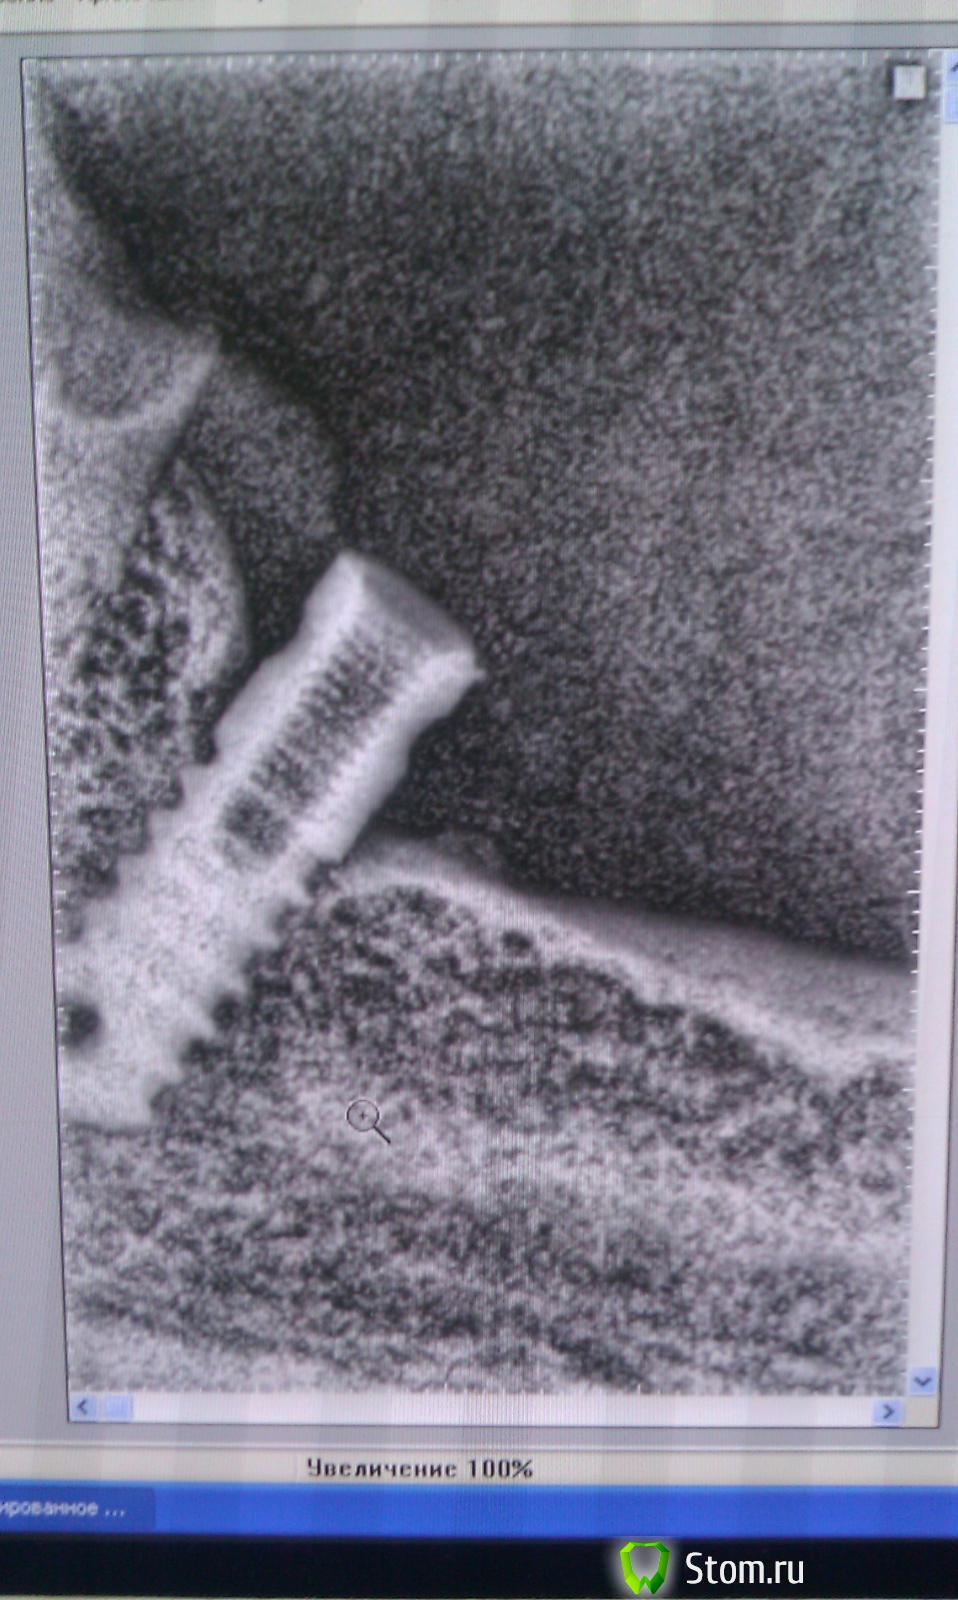

red_butler Опубликовано 4 июня, 2015 Поделиться Опубликовано 4 июня, 2015 Коллеги помогите с опознанием, подозреваю штрауманhttp://s015.radikal.ru/i331/1506/a4/69fe40e55adc.jpg Ссылка на комментарий

Чертков Александр Опубликовано 4 июня, 2015 Поделиться Опубликовано 4 июня, 2015 штрауман Полагаю он и есть Ссылка на комментарий

parallax Опубликовано 4 июня, 2015 Поделиться Опубликовано 4 июня, 2015 Похож, но не Штрауманн. У Штрауманна выраженная расходящаяся полированная шейка, которая располагается супракрестально. Здесь её нет. Как по мне, так это Liko-m. Ссылка на комментарий

red_butler Опубликовано 4 июня, 2015 Поделиться Опубликовано 4 июня, 2015 Похож, но не Штрауманн. У Штрауманна выраженная расходящаяся полированная шейка, которая располагается супракрестально. Здесь её нет. Как по мне, так это Liko-m.винт стоит 10 лет, это точно не ЛИКо и ЛИКоМ Все таки похоже на штрауман, с данной системой не работаем, если пациентка согласится оплачивать расходник - будем протезировать Ссылка на комментарий

Alex52 Опубликовано 4 июня, 2015 Поделиться Опубликовано 4 июня, 2015 Семадос, не? Ссылка на комментарий

syrovovec Опубликовано 4 июня, 2015 Поделиться Опубликовано 4 июня, 2015 Семадос думаю не, у него агрессивнее резьба Ссылка на комментарий

CToMaToJlor Опубликовано 11 июня, 2015 Поделиться Опубликовано 11 июня, 2015 (изменено) Коллеги помогите с опознанием, подозреваю штрауманhttp://s015.radikal.ru/i331/1506/a4/69fe40e55adc.jpgРаботаю со Straumann. Очень пожоже на Straumann standard plus. Платфому точно не скажу, скорее всего диаметр импланта 4.8 и платформа RN, Имейте ввиду много клонов, аналогов ( не очень распространенных в России). Что там с индентичностью протетики- большой вопрос.И к Лору его направьте через пару месяцев после реэндодонтии 16)))) не помешеает Изменено 11 июня, 2015 пользователем CToMaToJlor Ссылка на комментарий